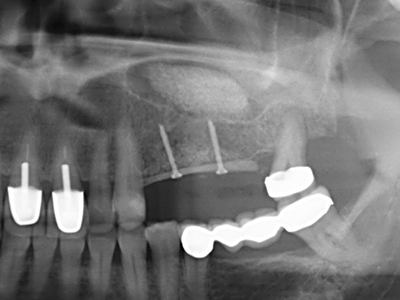

Como ya se ha demostrado en el pasado, básicamente cualquier procedimiento de cirugía de hueso representa una posible indicación para la cirugía piezoeléctrica. Así, la preparación del segmento móvil en la osteogénesis de distracción (fig. 23-25) y en la osteotomía de sándwich puede realizarse con piezas especiales, sin poner en peligro el suministro sanguíneo de la parte crestal, que resulta esencial para el éxito de ambas técnicas (González-García, Diniz-Freitas et al. 2008).

Para la extracción de implantes es posible realizar la preparación de una tapa ósea vestibular que, tras retirar el tornillo del implante, vuelve a fijarse y, de este modo, mantiene el contorno de la apófisis alveolar.

En la cirugía del seno maxilar surgen otros campos de aplicación: En este punto, tras la preparación concéntrica de una tapa ósea de la pared del seno maxilar (que suele tener forma trapezoidal), es posible eliminar patologías y cuerpos extraños del seno maxilar. La tapa ósea se repone después de finalizar la parte intra-antral de la operación y se asegura frente a una posible dislocación mediante cuñas o suturas adaptables.